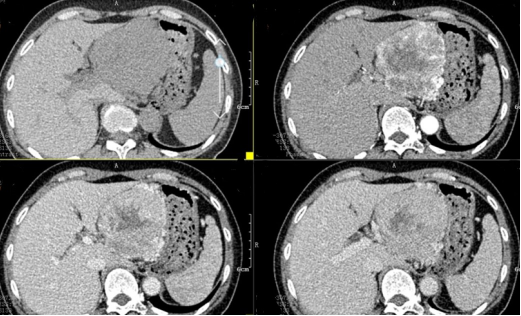

图1:上腹部CT显示胰腺巨大肿瘤

入院后,根据王女士病情,曹利平教授及其团队为她制定一套详尽的术前检查和治疗方案。首先,安排做上腹部增强CT,并建议其先穿刺活检明确病理。

“CT表现符合胰腺神经内分泌肿瘤,穿刺也证实无误,但是瘤体实在太大,直径约12cm左右,腹腔内的门静脉、肠系膜上静脉、脾静脉以及腹腔干这些重要血管统统包绕进去了,且与周围结肠系膜也有累及。”